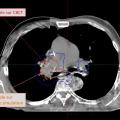

Innovations en radiothérapie

Dans le cadre de la prise en charge des cancers, la radiothérapie joue un rôle central, constituant une modalité de traitement utilisée chez plus de la moitié des patients à un moment de leur parcours thérapeutique. Bien qu’elle soit une composante essentielle des soins oncologiques, ses aspects techniques et ses évolutions récentes…